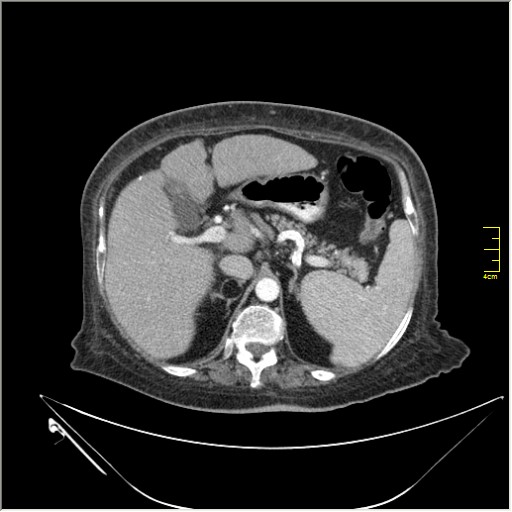

Весьма актуальная тема. Часто при проведении КТ исследования по тому или иному поводу, мы находим патологию, никак не связанную с клиникой пациента и не являющимся причиной обращения в кабинет КТ. Очень важно знать; как с этим быть, какие рекоммендации и действия необходимо предпринять. Для примера приведу одно наблюдение.

N.B. Все "находки" никак не были связаны с клиникой.

образование в правом надпочечнике

Incedentaloma правого надпочечника

Находки 2:

1.Образование правого надпочечника с плотностью жира, липома. Ничего делать не надо. По другим вариантам incidentalomas, Др. Капустин всё расписал.

2. Множество мелких конкрементов жёлчного пузыря, заполняющие до 50% просвета. С этим надо что-то делать. )))